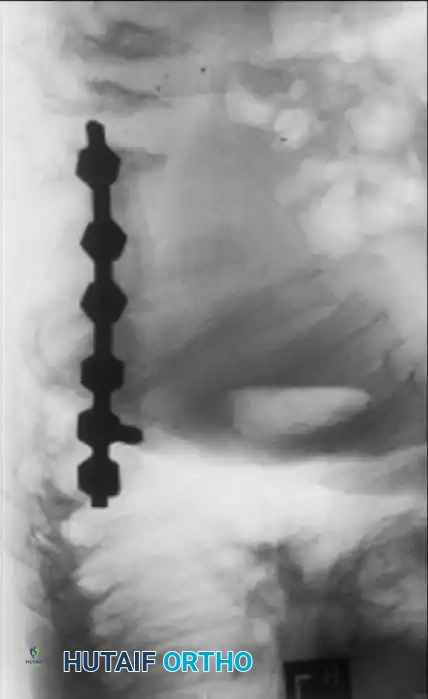

Fig. 38-219 B & C, Postoperative anteroposterior and lateral radiographs demonstrating successful spinal arthrodesis with pedicle screw instrumentation, restoring sagittal balance without neurological compromise.

Additional imaging demonstrating the complex osseous anatomy and pedicle morphology that must be navigated during instrumentation in skeletal dysplasias.